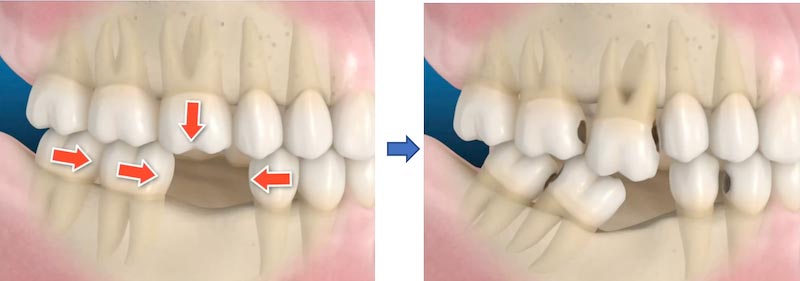

顳顎關節位在我們耳朵前方,負責控制下顎的張合。如果下顎往前、後、左右偏移,就會影響到咀嚼、說話、甚至全身姿勢。這種關節錯位引發的全身症狀,被稱為「顳顎關節偏移症候群(Neuromuscular TMJ Disorder)」。

顳顎關節與頭部、頸部、脊椎及全身的肌肉神經息息相關。當它偏移時,身體為了保持平衡會自動調整姿勢,進而導致一連串不適,如肌肉疲勞、神經壓迫、甚至影響視覺、聽覺、情緒與睡眠品質。

這些因素都會讓原本應該穩定的關節位置,逐漸產生偏移,影響咬合與全身健康。

► 關鍵是先評估出「正確的下顎位置」,就像做汽車四輪定位,再依狀況逐步修復。

治療結束後,可見下顎已恢復至正常位置